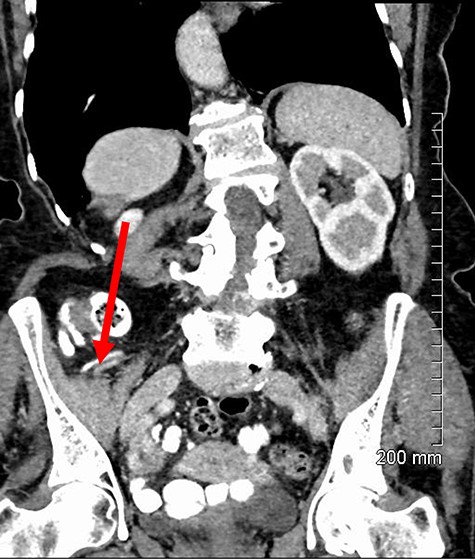

Repair was performed via a transinguinal (Lotheissen’s) approach. An incision was made just superior to the inguinal ligament and a femoral hernia was identified. The sac was dissected free and opened, revealing a gangrenous appendix (Fig. 2). There had been no preoperative suspicion for appendiceal involvement or strangulated contents, with normal lab studies and the appendix located remotely from the hernia on previous imaging (Fig. 3). The diagnosis of DGH was made intraoperatively. Abdominal access was achieved through the initial incision to facilitate an open appendicectomy. The mesoappendix and base of the appendix were ligated with sutures and delivered for further histology. The hernia sac was then transfixed and excised. A primary repair was performed with a non-absorbable suture.

Gangrenous appendix revealed following opening of femoral hernia sac.